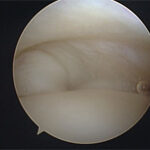

Segundo Stephen Snyder, os pontos articulares que devemos avaliar na artroscopia do ombro são:

- Tendão do bíceps e labrum superior;

- Ligamentos gleno-umeral superior, médio, tendão subescapular, labrum anterior, labrum inferior e superfície glenoide;

- Gleno-umeral anteroinferior e recesso axilar;

- Tendão supraespinhoso (articular), manguito posterior e “bare area”;

- Superfície articular umeral e labrum posterior.

Após a avaliação do espaço articular, reposicionamos o artroscópio para avaliar o espaço subacromial. Nesse local, podemos identificar patologias da bursa subacromial, do manguito rotador, do acrômio, do ligamento coracoacromial e da articulação acrômioclavicular.